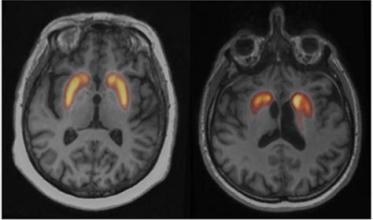

- Le Data Challenge Dat-Hub : dans le domaine de la neurologie, la Société Française de Médecine Nucléaire organise un challenge consacré aux syndrômes parkinsoniens. Les participants auront pour mission de développer un algorithme contribuant au diagnostic de ces syndrômes aux formes multiples. Des données d’imagerie cérébrale, appelées DatScan, de plusieurs milliers de patients seront mises à disposition pour le challenge.